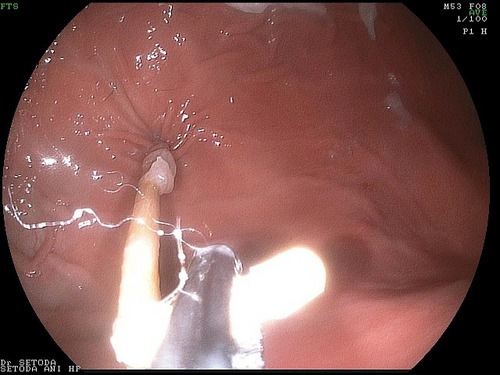

無事に体外に取り出したのが、このつまようじです。

DSC_5163.jpg

この、つまようじには、おいしい食べ物のにおいがしていたからペットが飲み込んでしまったのかもしれません。